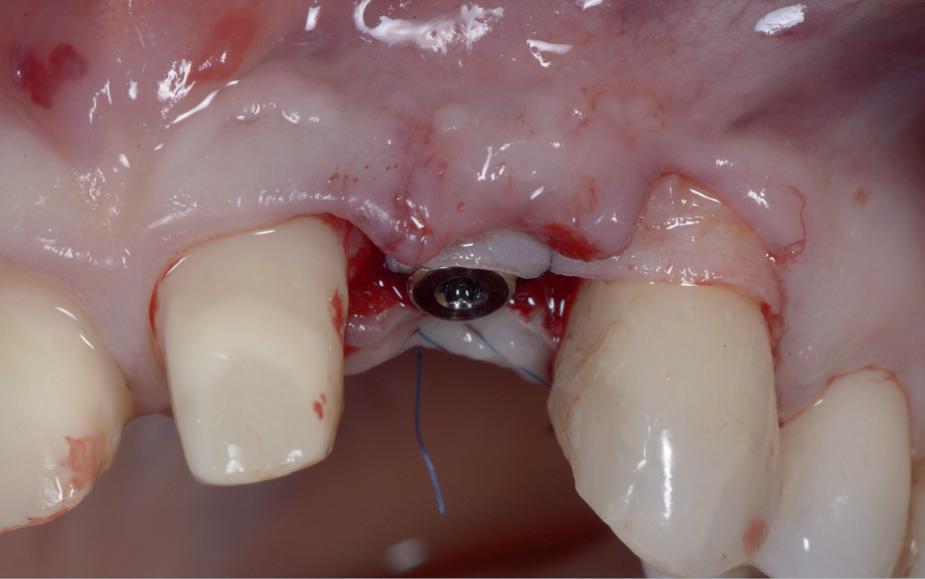

1a. Verlies van buccaal bot na immediaat plaatsing 1b. Jumping Gap 1c-j. Guided geplaatst met een tijdelijke kroon indirect vervaardigd

3a-f. Casus met gemis om primair te kunnen sluiten na fors defect als gevolg van ankylotische elementen. Externe resorptie na trauma en terugplaatsing op 13-jarige leeftijd.

Om alle bovenstaande redenen plaats ik momenteel, bij voorkeur, geen implantaten meer immediaat. Natuurlijk zijn er wel uitzonderingen. Maar die zijn jaarlijks inmiddels op één hand te tellen. Dat betreft alleen frontelementen met tenminste 2 mm autoloog bot buccaal (minder dan 0.5 % van de casussen volgens Kan et al.). Uiteraard dan guided geplaatst met een tijdelijke kroon indirect vervaardigd (afbeelding 1c-1j).